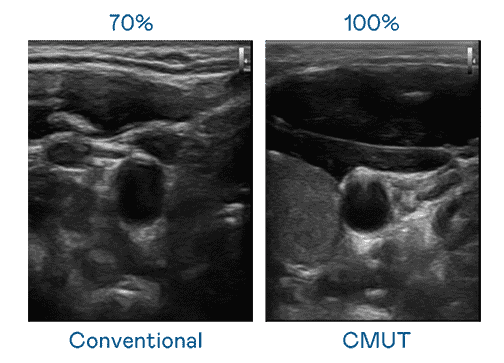

CMUT 技术是一种用电容式微机电元件来产生超音波讯号的技术。。。。与传统 PZT 压电式技术相比,,CMUT 频宽增加 30%,,,更宽频的超音波讯号让影像解析度大幅提升,,是实现高影像品质医疗超音波扫描、、、促进精准医疗发展的关键技术。。

大频宽带来超清晰影像

超音波影像的解析度高低,,首先取决于探头能发出的讯号频宽。。。OBPay CMUT 可提供高清晰的超音波讯号,,提供高频宽、、高灵敏度、、影像纹理细节更高的超音波影像,,,,协助医护人员缩短影像判读时间及利用精准的医疗影像进行诊断。。